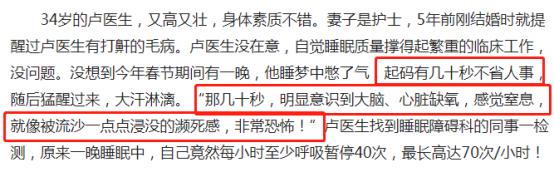

泰安一名35岁男子,在睡觉中呼吸暂停,不幸离世。他家人说,他平时身体健康,看不出任何问题。 34岁的卢医生,又高又壮。却在一次睡梦中差点断气,找到同事一检查,自己竟然每小时至少呼吸暂停40次,最高70次/小时!